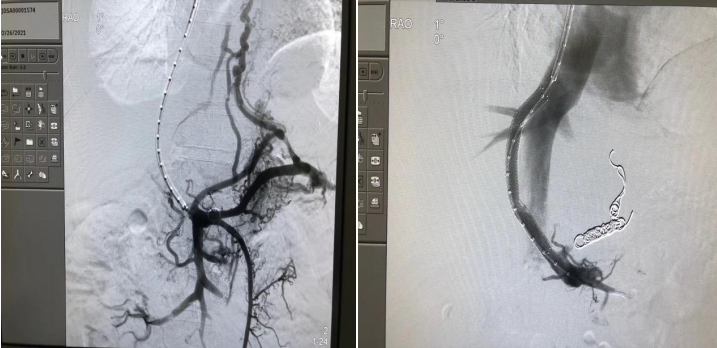

保障肝硬化失代偿期患者的生存,在很大程度上依赖于对门静脉高压的控制。门静脉高压的治疗除内镜及药物治疗外,介入技术在门脉高压诊治过程中正发挥着越来越重要的作用,肝胆胰介入手术之一-经颈静脉肝内门体静脉分流术(TIPS)已成为治疗门脉高压性消化道出血及肝硬化顽固性腹水的重要方法之一。TIPS治疗既可以治疗出血,又可以治疗门脉血栓,使门静脉血栓逐渐消失,不影响后续肝移植,也可以减少肝移植后门静脉血栓形成风险。

近30年来,TIPS技术发展可谓一波三折,随着近年来各种新材料、新技术的推广应用,介入又迎来了春天,TIPS和其他介入诊疗技术已经不断渗透到各个领域,取得令人满意的疗效,成为最具活力的学科。 “浙大一院肝胆胰介入中心”成立以来,每年完成TIPS手术近200例, 稳居全国前列。建立了浙江省最大TIPS病例库,已成为浙江省乃至全国最大的TIPS技术推广中心之一。本中心同时为中国大陆首批TIPS新型专用支架应用单位,止血有效率达95.7%。腹水缓解有效率达90%。孙军辉主任团队已经在省内外31家5g影院 推广开展或合作提升TIPS技术,惠及大量肝硬化门脉高压患者,多次受邀在国内省内外学术大会做TIPS专题报告,并协助省内医学中心建立区域TIPS技术推广中心。